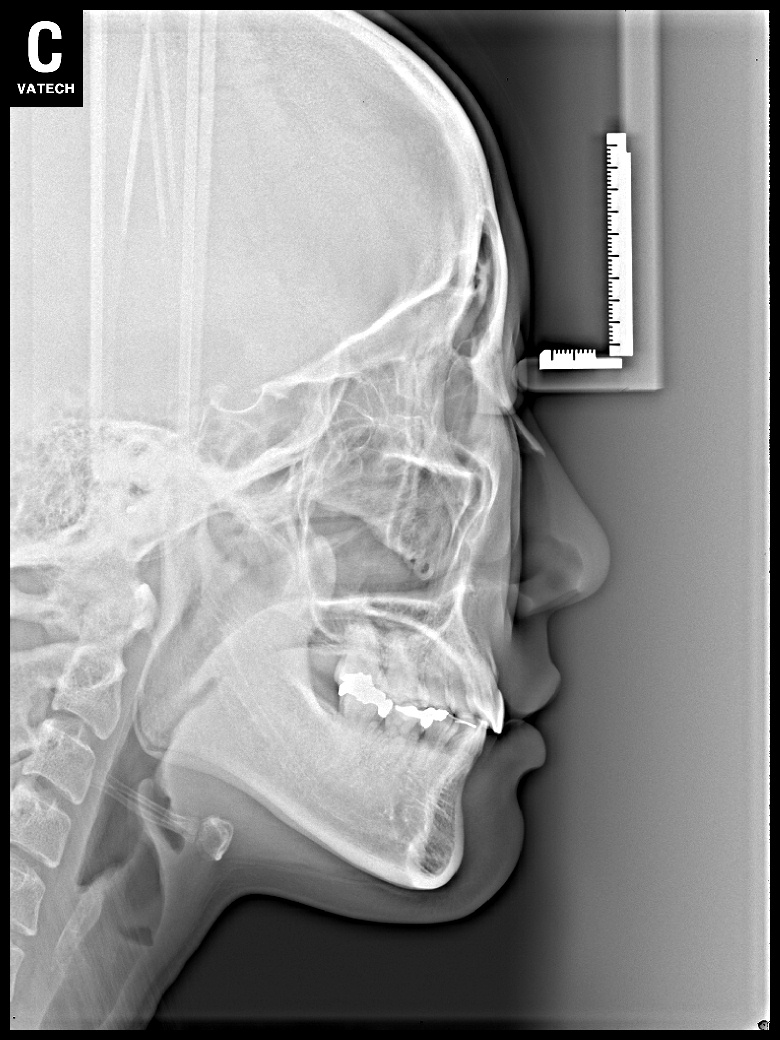

치료 후 사진입니다.